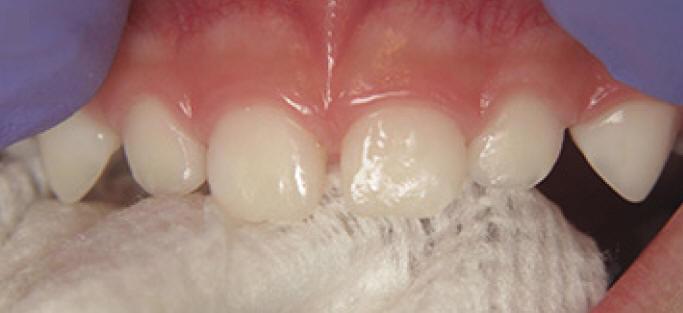

Técnica de aplicación profesional del barniz fluorado (Clinpro White Varnish)

1. Cepillado manual para eliminar placa bacteriana de la superficie dental

2. Ubicar rollos de algodón en el cuadrante que se va a trabajar

3. Secado de los dientes con gasa (figura 1)

4. Aplique una capa delgada de barniz de una sola vez, lo más rápido posible (figura 2) notará que el barniz se vuelve más firme, porque seca muy rápido en ambientes cálidos ó en contacto con los dientes.

5. Secuencia de aplicación:

• Arcada superior desde las molares hasta los incisivos: caras vestibular, proximal, oclusal  y palatino

• Arcada inferior desde las molares hasta los incisivos: caras vestibular, proximal, oclusal  y palatino (figura 3)

6. Luego de la aplicación del barniz el paciente no debe comer nada por las siguientes dos horas, solo puede beber agua.

7. No se debe cepillar los dientes el día de la aplicación.

Figura 1

Figura 3

Figura 2